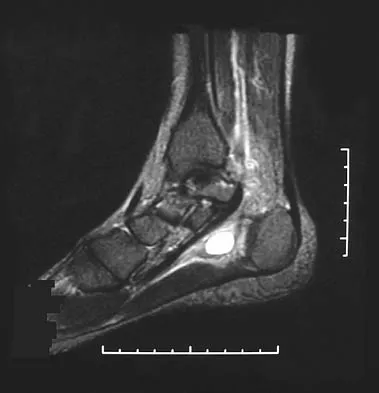

What is the most common long-term complication of the fracture shown in Figure 32?

The fracture pattern shown in the radiograph involves both a talar neck fracture and a talar body fracture. The body fracture propagates into the subtalar joint, with significant risk for the development of arthritis in that surface even with an anatomic reduction. In addition, Canale and Kelly reported a 25% incidence of malunion of talar neck fractures, with varus angulation occurring most frequently. Of these patients, 50% required a secondary surgical procedure because of the development of degenerative joint disease of the subtalar joint. Canale ST, Kelly FB Jr: Fractures of the neck of the talus: Long-term evaluation of seventy-one cases. J Bone Joint Surg Am 1978;60:143-156.